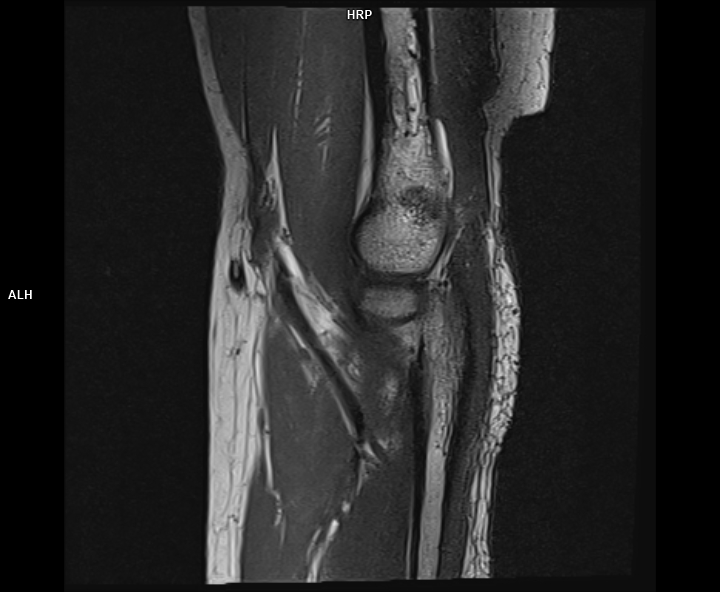

Figura 1: achiziție sagital T1 la nivelul cotului cu evidențierea tendonului de inserție inferioară a mușchiului biceps brahial ce este retractat superior